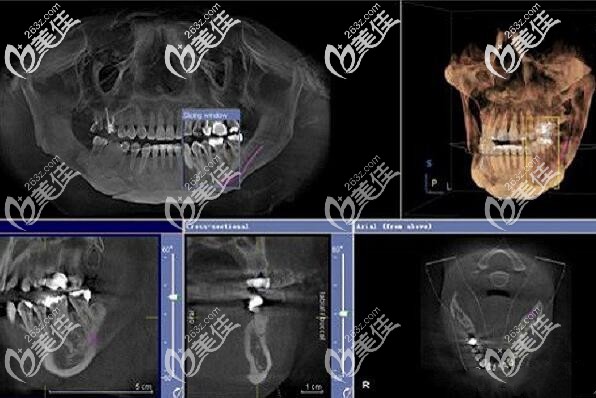

种植牙前的CT片▲

“医生说自己的牙槽骨萎缩,只有5MM左右,如果做传统种植牙需要先植骨,也就是说多做一次手术,还多花钱;如果做all-on-4全口种植牙,植体可以斜着植入,上下各植入4颗植体就能恢复全口的咀嚼功能,关键是少受罪、少花钱、还能当天吃东西。”

这是大叔做完全口种植牙1年后的CT片▲